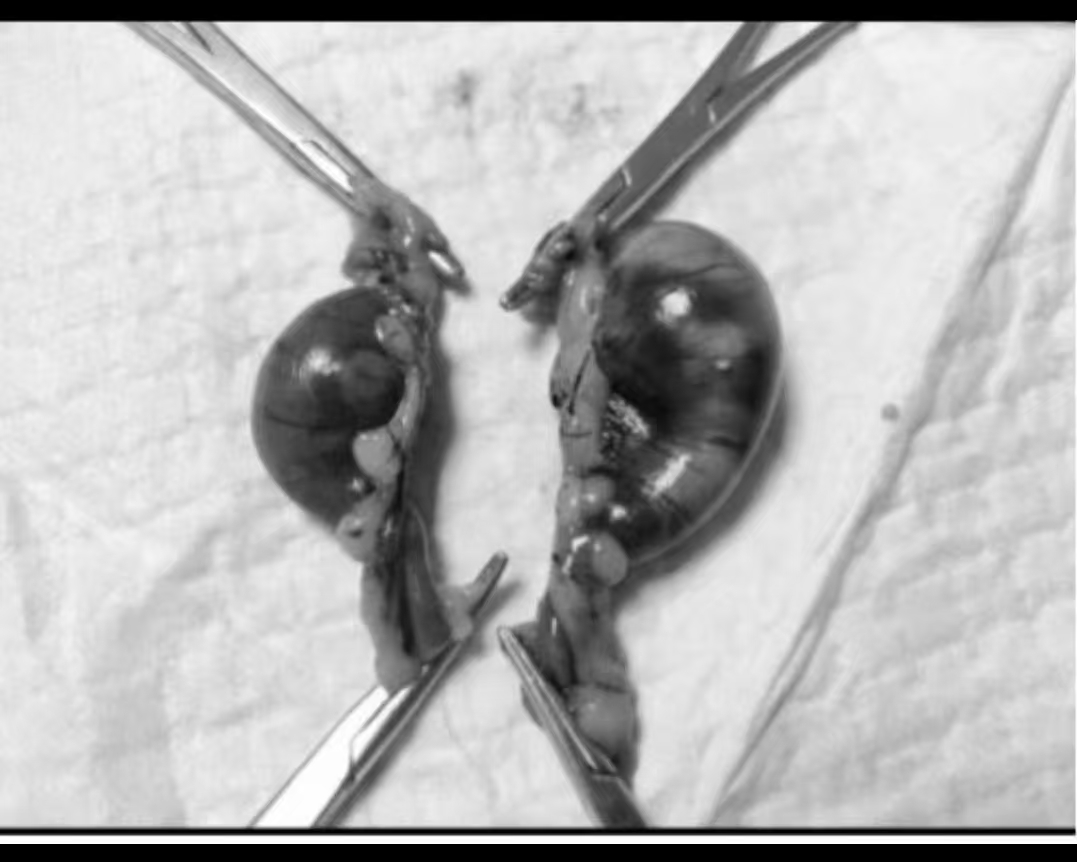

Given that the fetuses were no longer alive, an emergency cesarean section was performed to remove the non-viable fetuses. Additionally, the ovaries and uterus were removed to prevent any future complications and to ensure the long-term health of the rat.